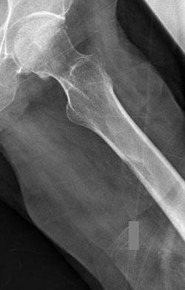

A 65-year-old male who underwent a cementless total hip arthroplasty (THA) 15 years ago presents with new-onset thigh pain. Radiographs reveal eccentric positioning of the femoral head within the acetabular shell and large retroacetabular and proximal femoral radiolucencies.

What is the primary biological mediator released by macrophages that directly stimulates osteoclastogenesis and is responsible for the observed bone loss?

Explanation

The radiograph demonstrates particle-induced osteolysis, secondary to polyethylene wear debris. When macrophages phagocytose these particles, they release pro-inflammatory cytokines, most notably TNF-a, IL-1, and IL-6. These cytokines stimulate the RANK/RANKL pathway, activating osteoclasts and leading to significant periprosthetic bone loss. IL-10 and IL-4 are anti-inflammatory cytokines, while IFN-y actually inhibits osteoclastogenesis.